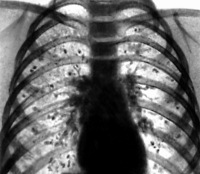

В подавляющем большинстве случаев гистоплазмоз протекает латентно. Острый гистоплазмоз легких описан как эпидемическая болезнь с инкубационным периодом 1- 2 нед. В легких случаях протекает в виде острого респираторного заболевания и заканчивается выздоровлением через 10 - 15 дней. Рентгенологическое исследование выявляет в легких малочисленные мелкие инфильтраты, описываемые как «снежная буря», «метель», «ватные хлопья» Тяжелые случаи болезни могут напоминать атипичную хроническую пневмонию и продолжаться 8 -10 мес и более. Характерным является несоответствие скудных данных, полученных при перкуссии и аускультации, и выраженных рентгенологических изменений в виде обширной двусторонней интерстициальиой инфильтрации, часто сопровождающейся увеличением лимфатических узлов средостения и тени корней легких. Частым исходом процесса является милиарная кальцификация легких.

Иногда гистоплазмоз легких протекает с образованием гистоплазмомы - большого округлого инфильтрата, трудноотличимого от рака легкого. В ряде случаев при гистоплазмозе преобладают изменения со стороны лимфатических узлов корня легкого, что обусловливает стснозирование сосудистых и бронхиальных стволов, их обтурацию, возникновение ателектазов, синдрома средней доли.

Для вторичного хронического диссеминированного гистоплазмоза легких характерны более крупные рассеянные очаги или инфильтративные фокусы, склонные к распаду, часто сочетающиеся с полилимфоаденитом, гепатолиенальным синдромом, анемией и лейкопенией.